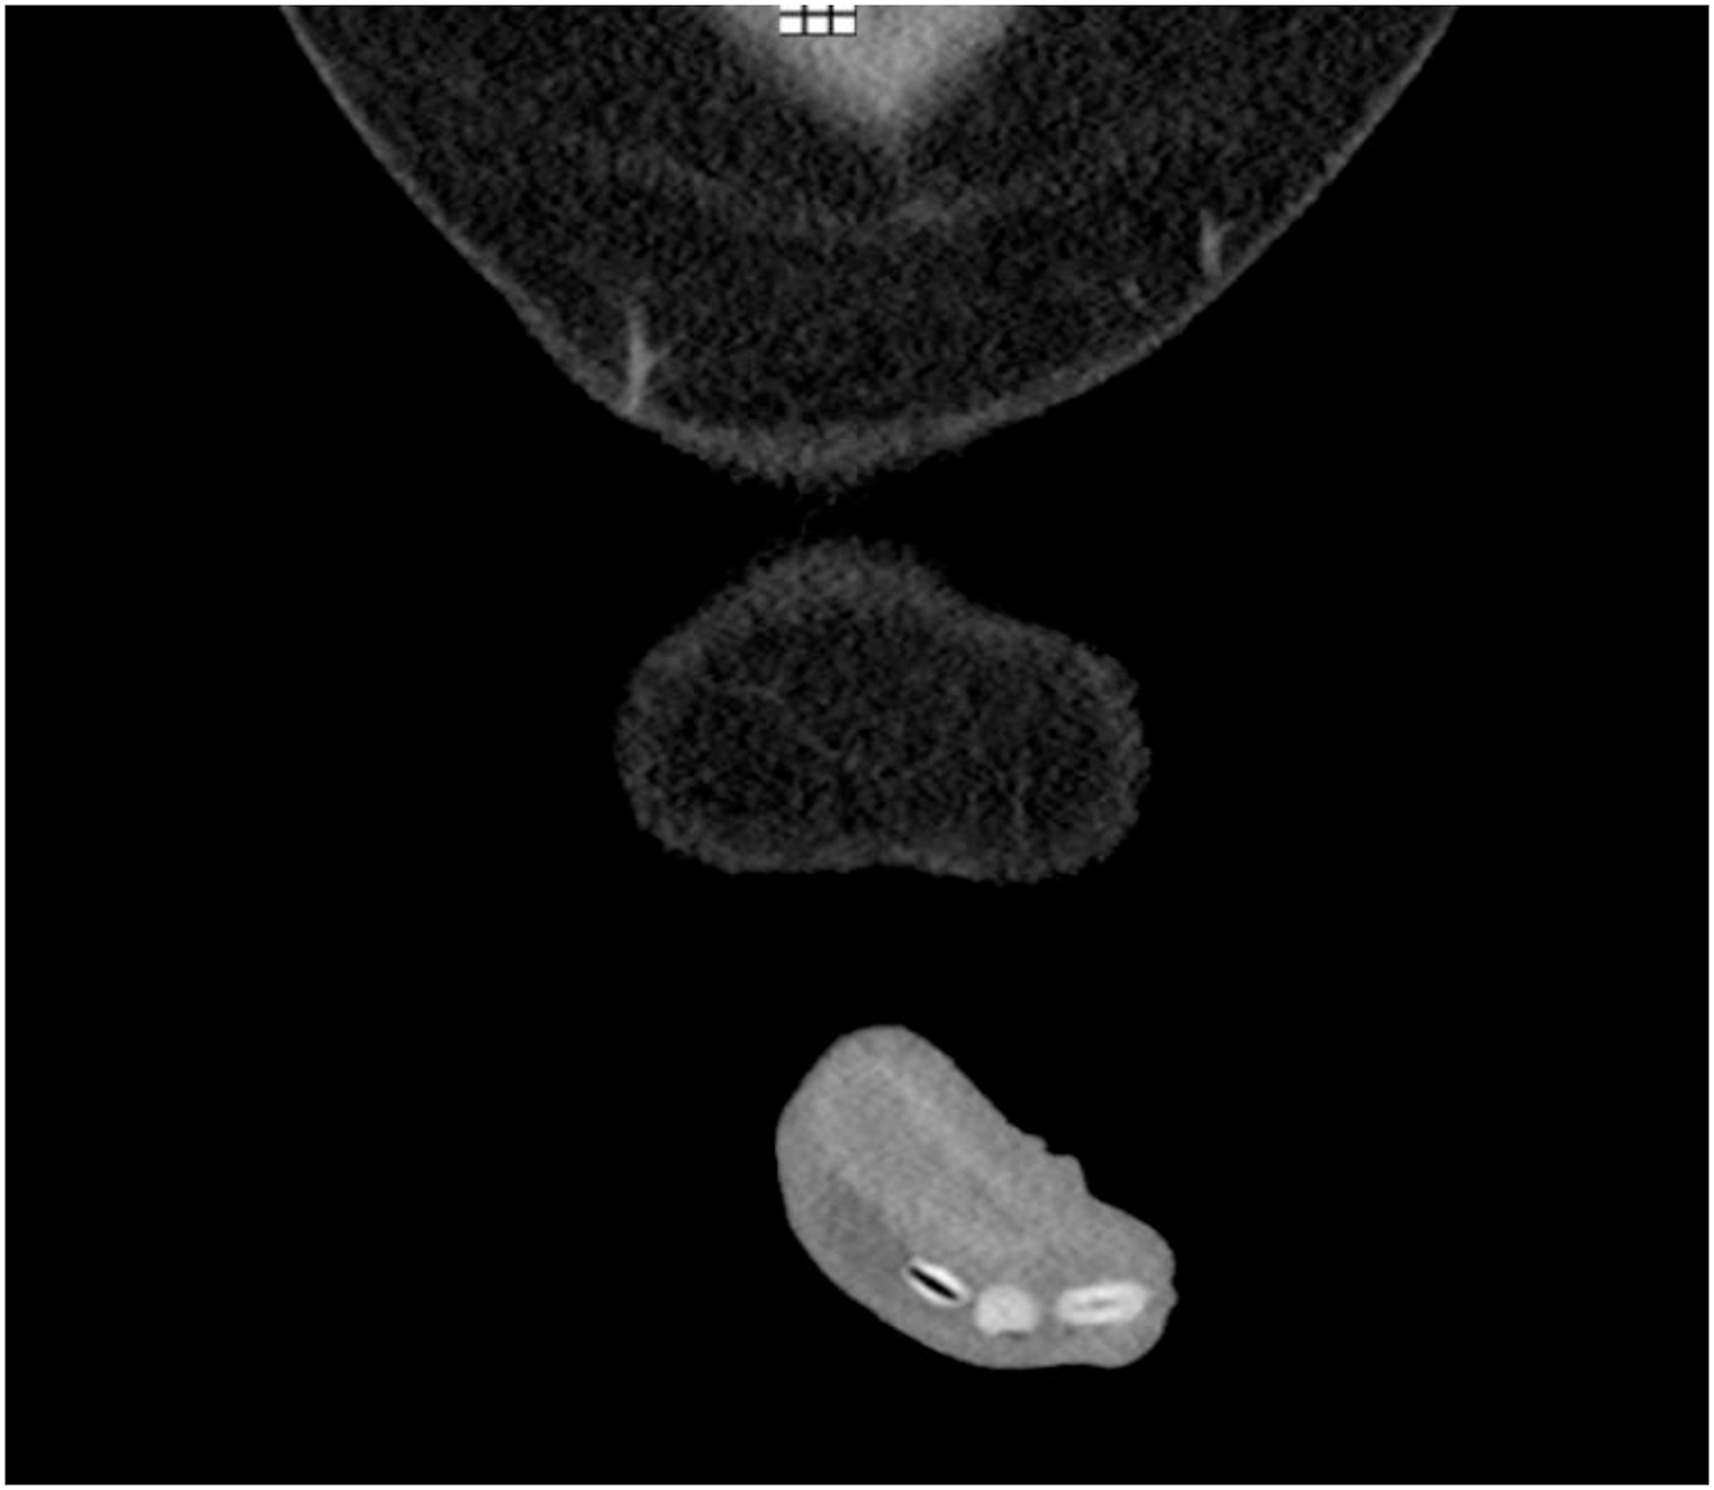

अस्पतालमा पनि निकै समय लगाएर कठिनाईका साथ डाक्टरहरुले उक्त मानिसको यो-नां’गबाट सिमीका गेडा बाहिर निकाल्न सफल भएका थिए। उपचार गर्नु अगाडी डाक्टरहरुले उनको यौ-नां’गको सिटी स्क्यान गर्दा नलीभित्र १५ मिलिमिटर साइजका ६ वटा सिमीका गेडा देखिएका थिए। यौनांग भित्र रहेका ६ ओटा गेडा मध्ये एउटा गेडा डाक्टरहरुले क्रिम लगाएर हातको मद्दतले नै बाहिर निकालेका थिए।

तर अन्य ५ ओटा गेडा भने त्यसरी निकाल्न नसकेपछि शल्यक्रिया नै गर्नु परेको हो। ती मध्ये ४ ओटा सिमीका गेडा उनको यौ’नां-गको बीच भागसम्मै पुगेका थिए भने एउटा त मुत्रथैलीभित्री छिरेको थियो। अहिले भने उक्त व्यक्तिको स्वास्थ्य अवस्था स्थिर रहेको डाक्टरहरुले बताएका छन्।